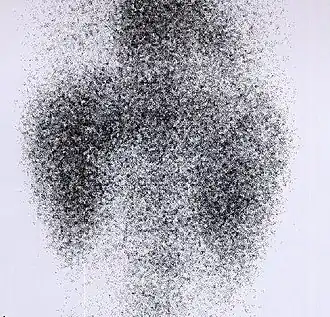

DMSA scan

![]() Decreased Tc99m-DMSA uptake in both kidneys, suggestive of renal failure. | |

A DMSA scan is a radionuclide scan that uses dimercaptosuccinic acid (DMSA) in assessing renal morphology, structure and function. Radioactive technetium-99m is combined with DMSA and injected into a patient, followed by imaging with a gamma camera after 2-3 hours.[1] A DMSA scan is usually static imaging, while other radiotracers like DTPA and MAG3 are usually used for dynamic imaging to assess renal excretion.[2]